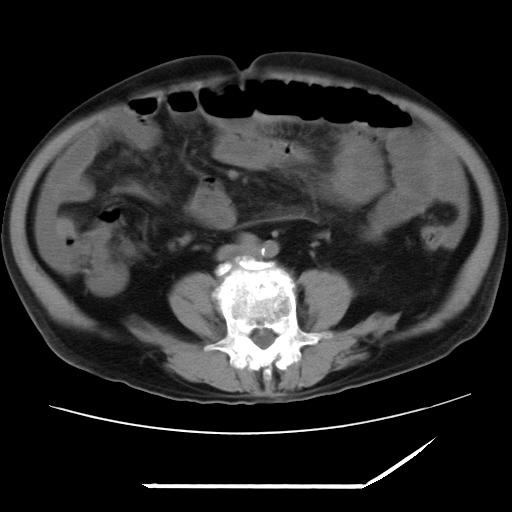

以下是引用zxl51642在2009-8-12 18:55:00的发言:[br]1、肠系膜脂肪浑浊,密度增高,腹水,支持腹膜炎诊断;2、右肾盂及输尿管中段结石,左输尿管起始段结石;3、胆囊切除术后改变?4、双侧胸膜腔少量积液;5、胰腺体积不大,勾勒清楚,肾前筋膜无增厚,不支持胰腺炎,请结合血尿淀粉酶及临床。

以下是引用黑白光影在2009-8-12 22:06:00的发言:[br][quote]以下是引用zxl51642在2009-8-12 18:55:00的发言:[br]1、肠系膜脂肪浑浊,密度增高,腹水,支持腹膜炎诊断;2、右肾盂及输尿管中段结石,左输尿管起始段结石;3、胆囊切除术后改变?4、双侧胸膜腔少量积液;5、胰腺体积不大,勾勒清楚,肾前筋膜无增厚,不支持胰腺炎,请结合血尿淀粉酶及临床。